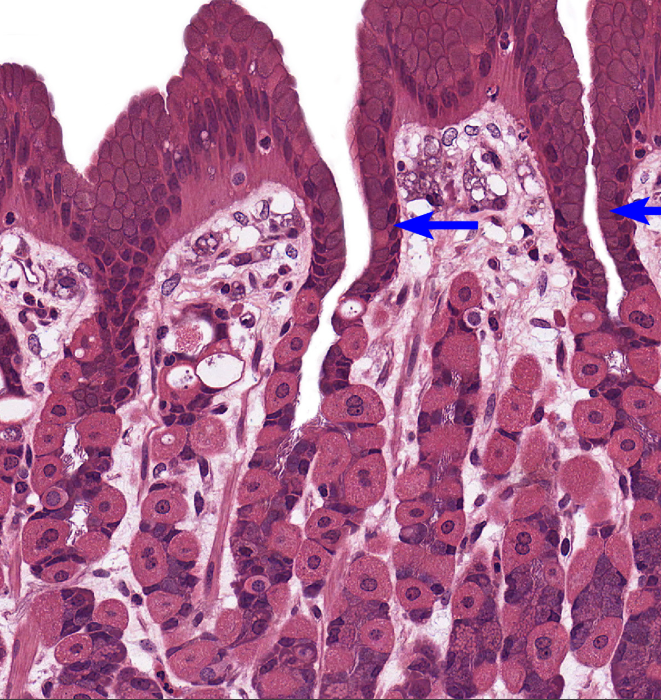

Stomach

NOTICE: THE DEEP GASTRIC PITS WITH DARK STAINED GASTRIC GLANDS AROUND THEM AND NOT MANY GOBLET CELLS